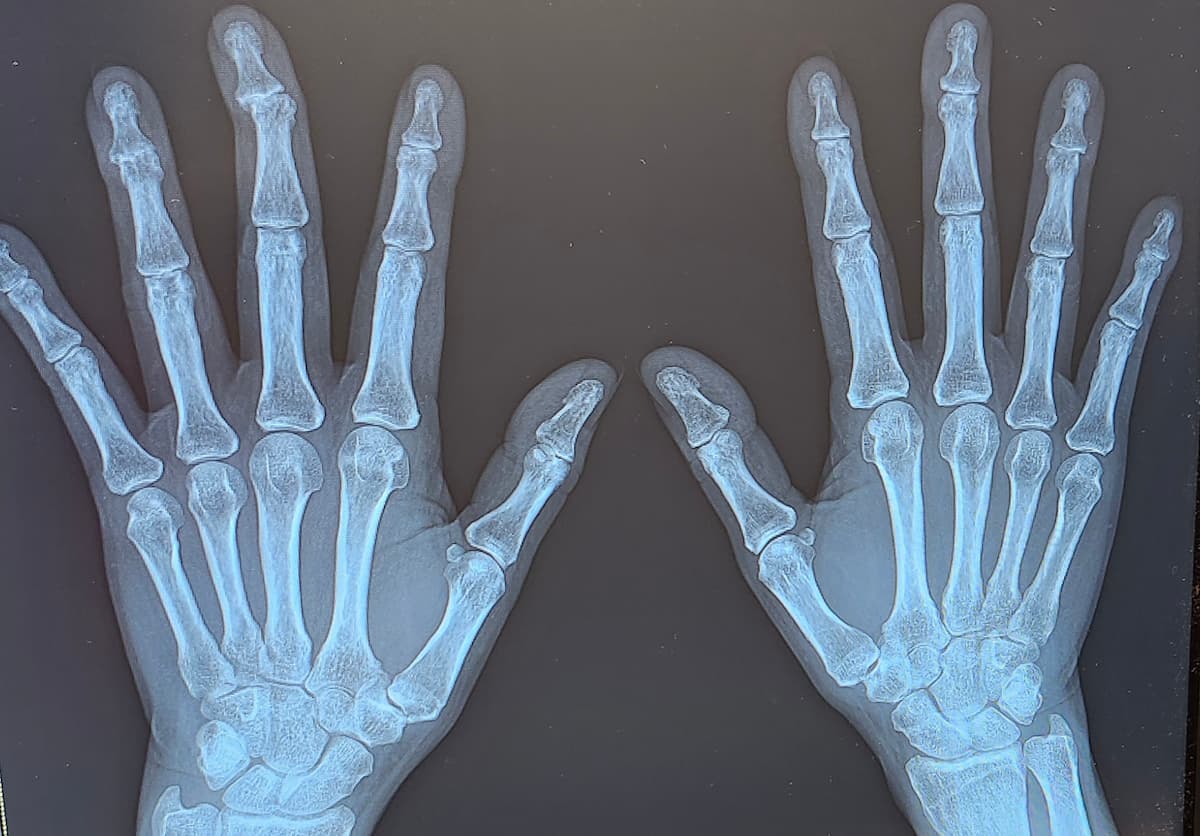

1年に1回の手足のレントゲンを撮ってもらいました。

でも先生の許可をいただいてレントゲン画像を撮影してきました。

ヘバーデン結節で指が大きく曲がってしまいました

ヘバーデン結節がとてもひどくて、

左中指の第一関節は大きくズレてしまっているのが分かると思います。

あとは左右の薬指(特に左)の第一関節も、

間隔が狭くなってしまっていて腫れと痛みがあります。

レントゲン画像を見ても、

右の薬指より左の方がずいぶん太いのは腫れているからです。